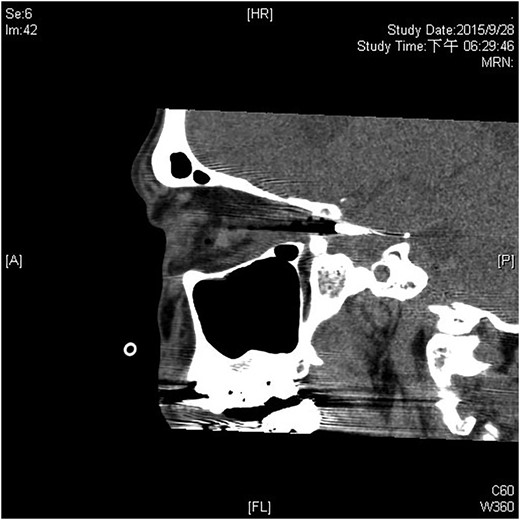

A 60-year-old man was admitted to our medical ward due to aspiration pneumonia. He had a medical history of diabetes mellitus, end-stage renal disease; a tuberculosis bacilli-related thoracic spine infection with paraplegia, and a previous coronary artery bypass graft. During his third day at the hospital, he obtained a ballpoint pen and inserted it into his left eye. On physical examination, the patient appeared to be alert with normal vital signs. The ballpoint pen protruded from his left upper eyelid; it was firmly lodged in his left medial orbit between the globe and nose, causing left eye proptosis (Fig. 1). Neurologic examinations revealed that the patient was neurologically intact except for complete left ophthalmoplegia. Brain CT scanning revealed a tubular foreign body that was located in the anteroposterior plane extending from the orbital apex and directly into the parasellar region (Fig. 2). The metallic portion of the foreign body was entrapped in left optic canal (Fig. 3). There was no evidence of intracranial hemorrhaging or a rupture in the globe (Fig. 4). The patient was treated with high-dose steroids to protect the optic nerve. The plastic ballpoint pen and metallic tip was withdrawn from the orbit smoothly at bedside, and no craniotomy was required. The ballpoint pen had been inserted to an estimated depth of 7 cm through the eyelid and into the orbit. The patient was then transferred to the ICU for close neuro-observation. We initiated intravenous broad-spectrum antimicrobials and vancomycin therapy and continued these medications for three weeks. A psychiatrist was consulted for a complete psychiatric evaluation and suicide prevention. The follow-up CT scan showed no retained foreign bodies or intracranial hemorrhaging (Fig. 5). At the last follow-up examination 2 months after the injury, the patient presented with complete left ophthalmoplegia and blepharoptosis but intact visual function.

The follow-up CT scan shows residual hematoma in the orbital cavity; no retained foreign bodies or intracranial hemorrhaging.